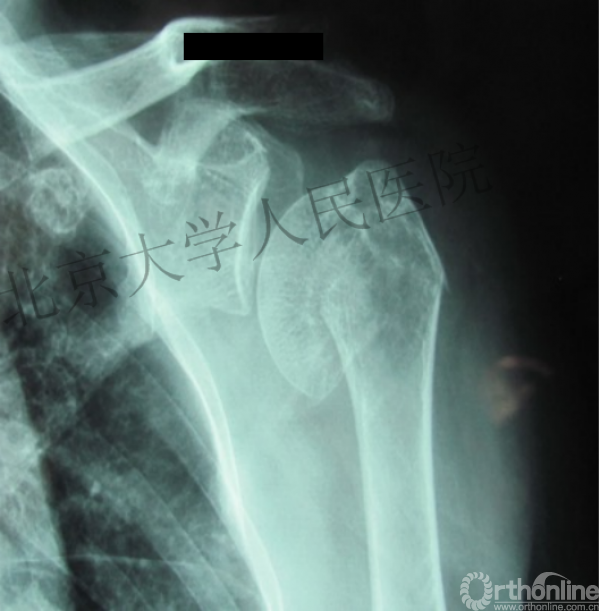

复位良好的标准:颈干角:135°,大结节与肱骨头距离:8mm

术后3月随访:继发性颈干角变小22°(5-82),肱骨头内翻,达46%

严重影响了患者的生活质量